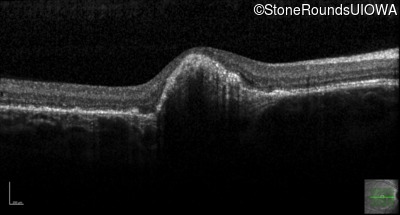

Optical Coherence Tomography - Left - 20/20 sc

Exemplar / OCT Stack

OCT Stack